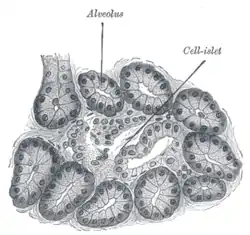

Section of pancreas of dog. X 250. | |

Alveoli of lacrimal gland.

Alveoli of lacrimal gland. Human submaxillary gland. At the right is a group of mucous alveoli, at the left a group of serous alveoli.